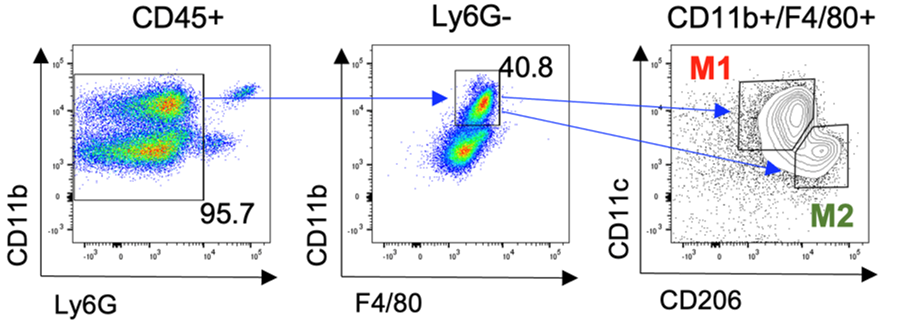

신경면역학 실험실(Neuroimmunology Laboratory)은 신경계와 다양한 말초조직 간의 상호작용을 연구합니다. 특히 말초조직 또는 면역세포를 조절하는 자율신경 신경회로를 발굴하고 작용기전을 밝힘으로써, 대사장애, 만성 염증성 질환, 종양, 근감소증 등을 극복하는 연구를 수행합니다.

신경계-면역계 상호작용 연구

- 연구주제 : 비만 및 대사장애 발생을 조절하는 신경계-면역계 상호작용 연구

- 연구주제 : 암 성장과 종양미세환경을 조절하는 신경회로 기전연구